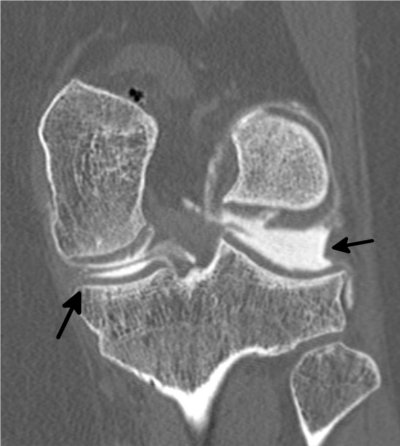

Genou

Calcifications méniscales (flèche de droite) Calcifications méniscales

Séquelles de ménisectomie (flèche de gauche)

Chondropathie fémorale (atteinte du cartilage) Fissure du ménisque interne

(flèche du haut)

Kyste méniscal (flèche du bas)